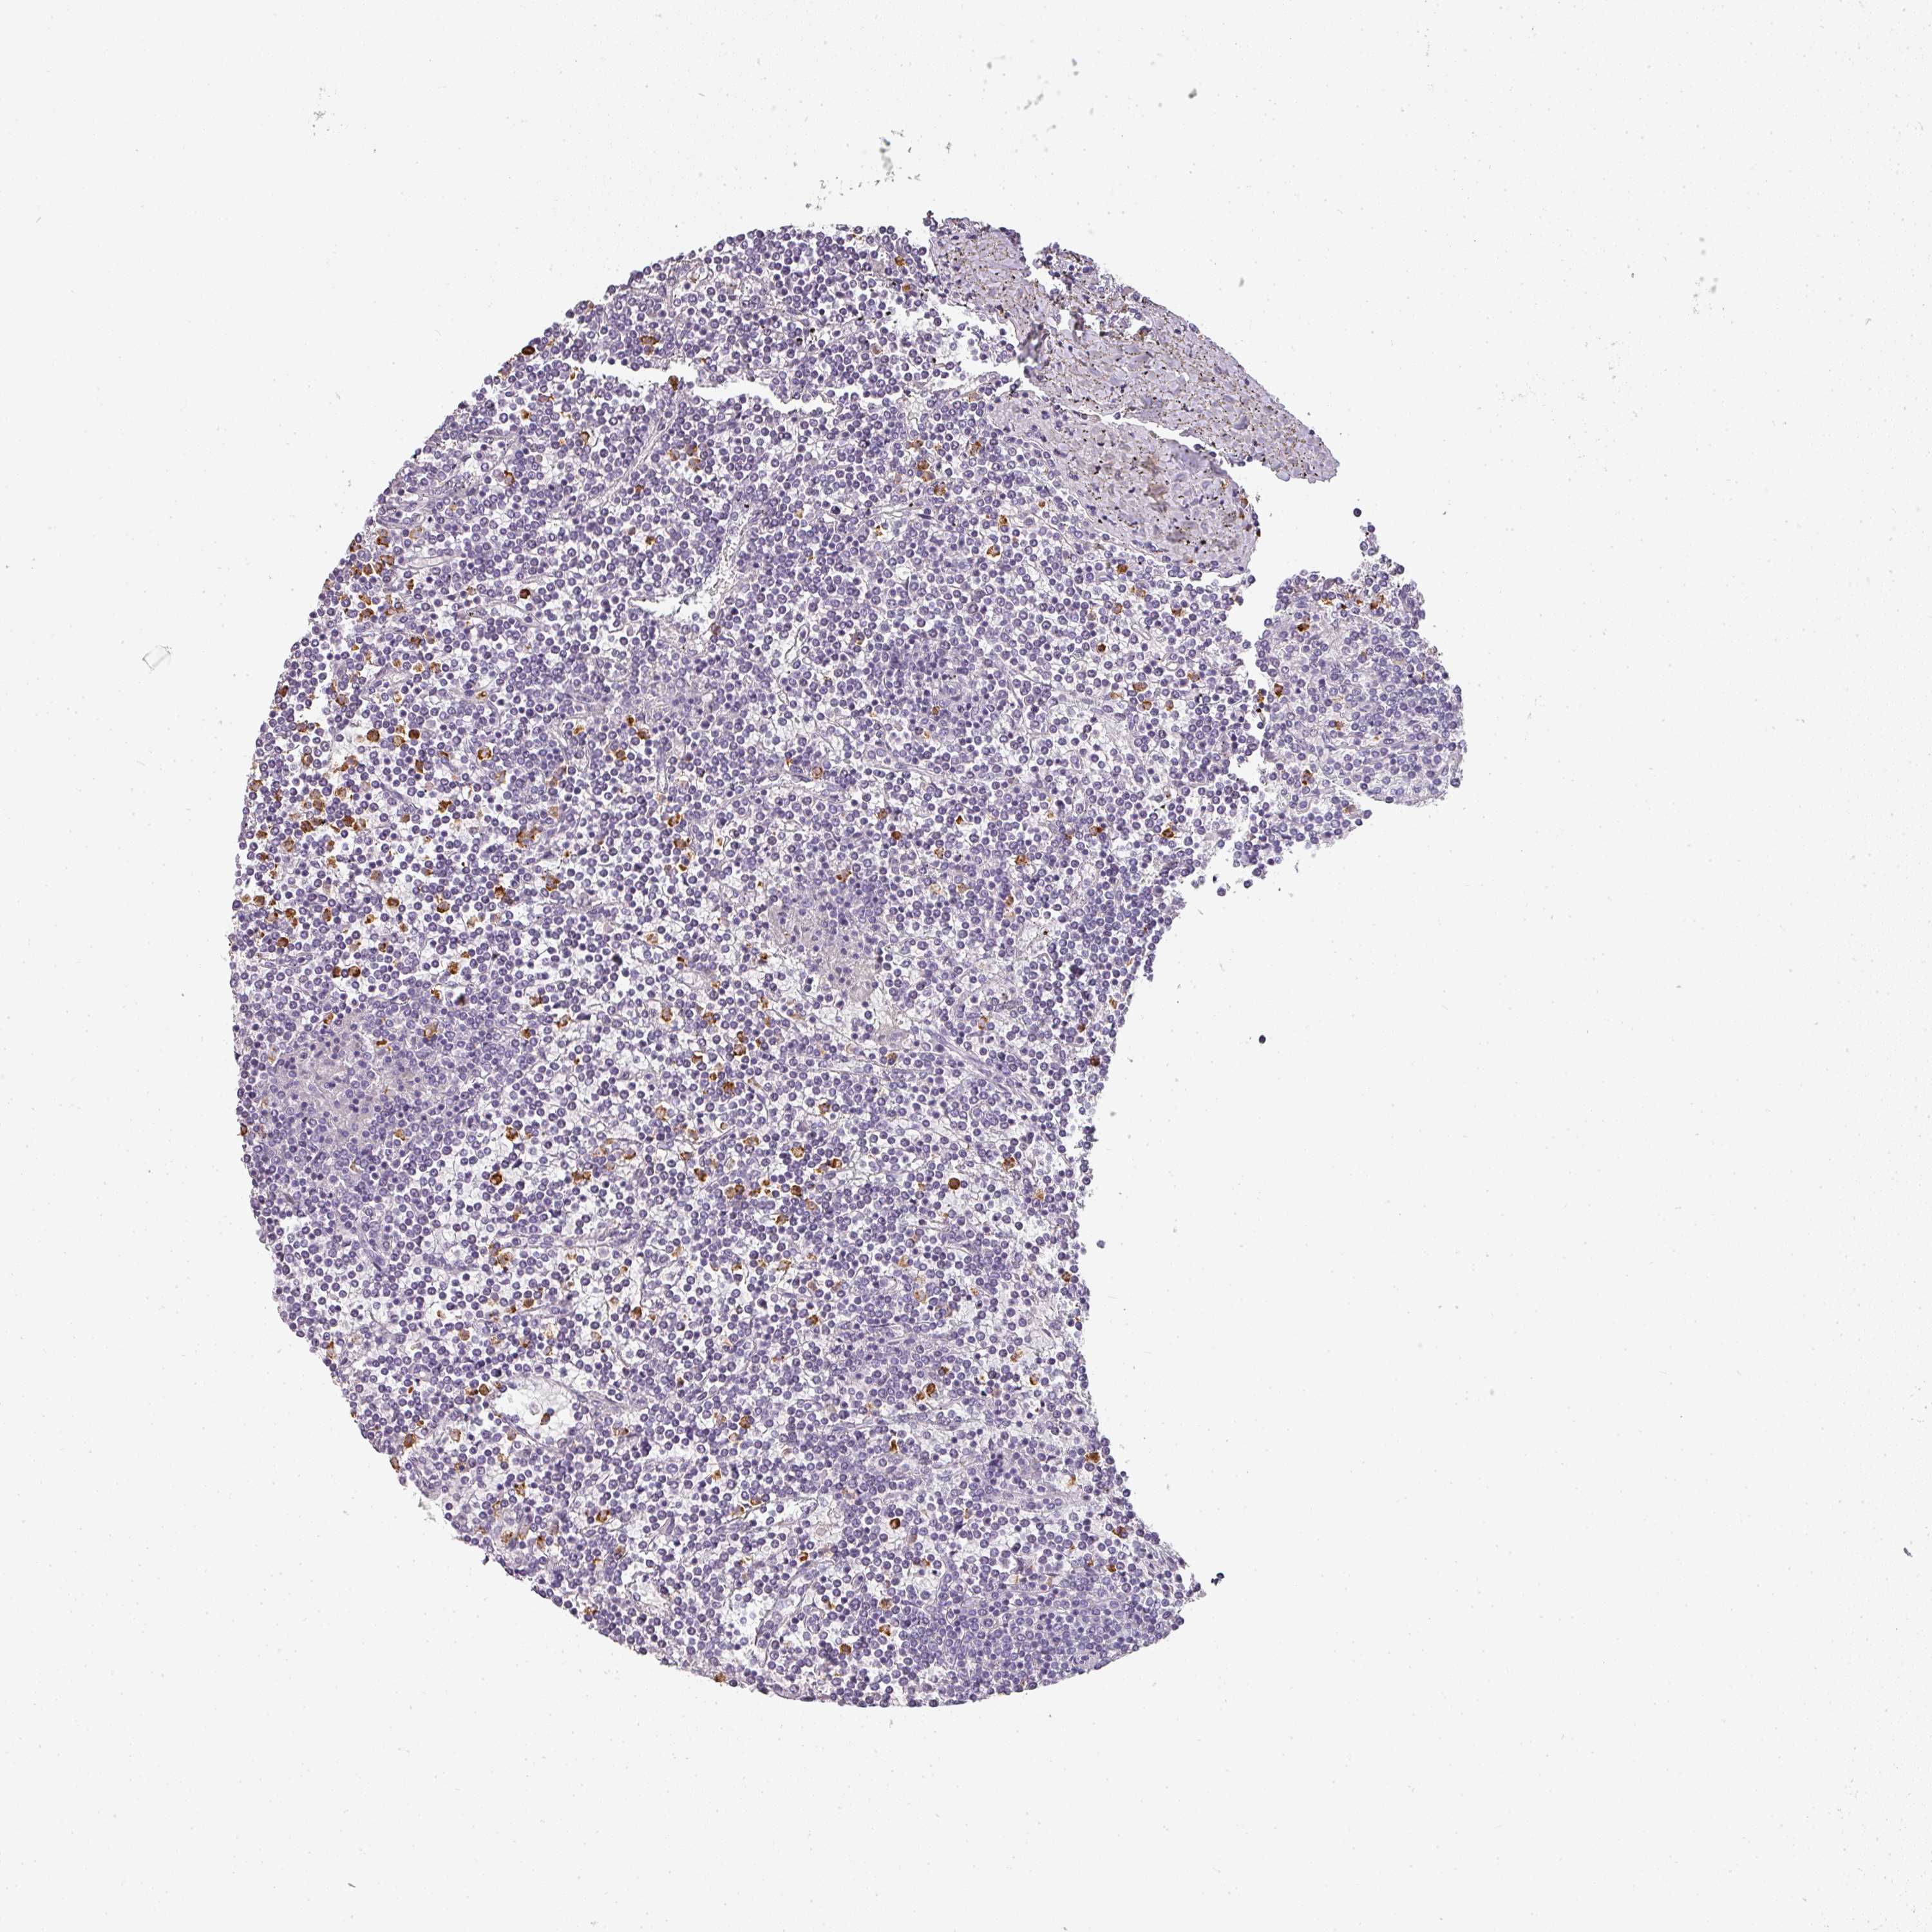

LYMPHOMA - Protein expressioni

A mouse-over function shows sample information and annotation data. Click on an image to view it in a full screen mode. Samples can be filtered based on level of antibody staining by selecting one or several of the following categories: high, medium, low and not detected. The assay and annotation is described here.

Each image is clickable and will lead to virtual microscopy that enables deeper exploration of all samples and also displays staining intensity scores, fraction scores and subcellular localization as well as patient and tissue information for each sample.

Antibody HPA029874

Hodgkin's disease, NOS

Malignant lymphoma, non-Hodgkin's type, High grade

Malignant lymphoma, non-Hodgkin's type, Low grade